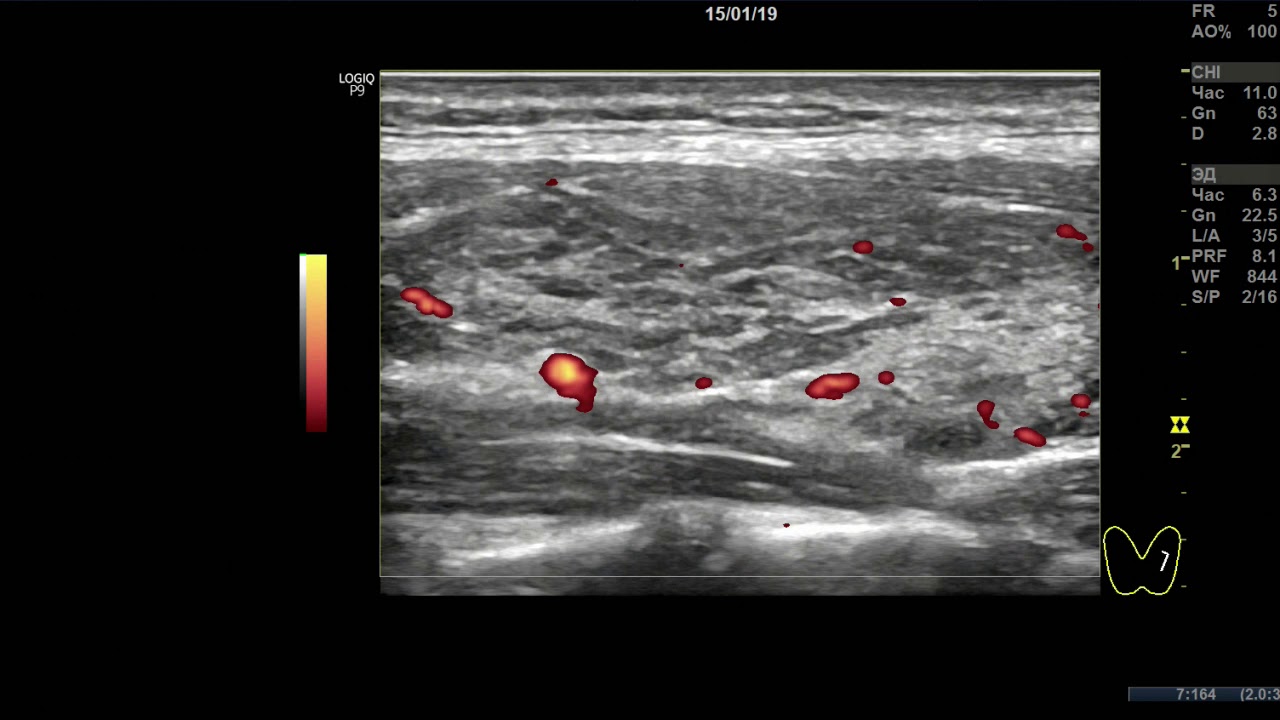

УЗИ узлового процесса щитовидной железы. Папиллярная карцинома (рак).

УЗ-признаки тотального диффузного и узлового процесса щитовидной железы, с малыми явлениями мелко-долькового деструктивного преобразования, мало выраженной внутридольковой регенерации малой лимфоцитарной инфильтрацией, правостороннего малого двухузлового процесса, на стадии начального истощения и развития (TI-RADS 2) и левостороннего одноузлового малодолевого процесса на стадии умеренного истощения (TI-RADS 5). Напряжение ткани железы (по интенсивности кровотока) нормально справа, мало усилено слева, узла справа – мало активно. Внеузловая ткань железы, выглядящая относительно полноценной гормонообразующей, составляет около 70-80%. УЗ-признаки метастазов 2-х лимфоузлов шеи слева.